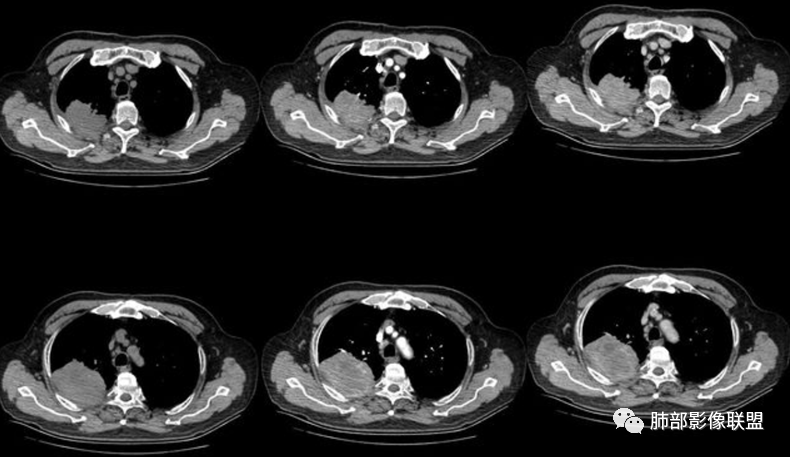

南边:今天的病例肺内部分基本都是炎性特点,问题就在于胸膜。

糊墙:肺内病灶不侵犯壁层胸膜或以外,与壁层胸膜相对而言分界清楚。

栽赃:病灶侵入壁层胸膜及胸膜外脂肪间隙、胸壁其他结构等,相对在病灶中央区域,与胸膜分界不清。

南边:看肺内病灶与胸膜分界清,增强后强化不一致,需要综合分析。

这是糊墙。

这就栽赃。都突到外面去了。

看看这个,骨头都侵袭了。

今天的病例有些伪影。

看起来就觉得放射状伪影。

我就不知道这些是胸水,伪影导致密度增高?还是胸膜增厚?

我只是邓较瘦:今天平扫的像栽赃, 增强感觉是增厚的胸膜。

南边:一般这类侵袭,是中央地带毛刷状延伸到胸膜内。

而且旁边这么宽的少,所以觉得很奇怪,不太符合,我是怀疑与照片有关。

你对比一下两侧的密度。肌肉密度不一样。

我只是邓较瘦:南大这个我感觉局部似乎是栽赃呢 箭头那里是啥?

南边:栽赃是这样过去的,中间不会脂肪间隙清晰。

胸壁的组织,除非你怀疑胸壁转移结节。

转移淋巴结。

局部侵犯。有差异。

我只是邓较瘦:这个是侵犯出去不是淋巴结吧?

南边:不是,你看看强化与淋巴结不一致。

我只是邓较瘦:强化与肿瘤差不多。

南边:是。